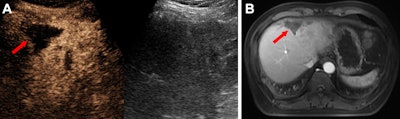

Images depict a 49-year-old male participant with hepatocellular carcinoma following downstaging therapy. (A) Transverse dual contrast-enhanced ultrasound (CEUS) image (left) and B-mode image (right) show the tumor lesion. (B) Image shows an axial contrast-enhanced MRI scan of the tumor lesion. Both CEUS and contrast-enhanced MRI reveal no evidence of residual viable tumor (arrow). Histopathologic analysis further confirmed the absence of residual viable tumor.RSNA